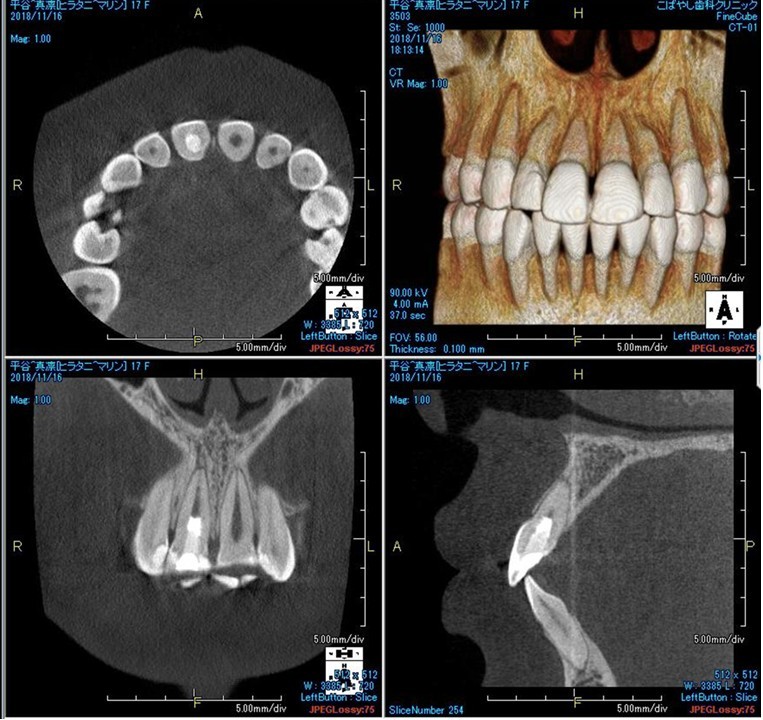

(図29)初診時のCBCT像

上1番の根尖周囲に透過性のレントゲン像が確認できる。唇側皮質骨の消失の可能性も予測でき、歯髄壊死の可能性が高いと考える